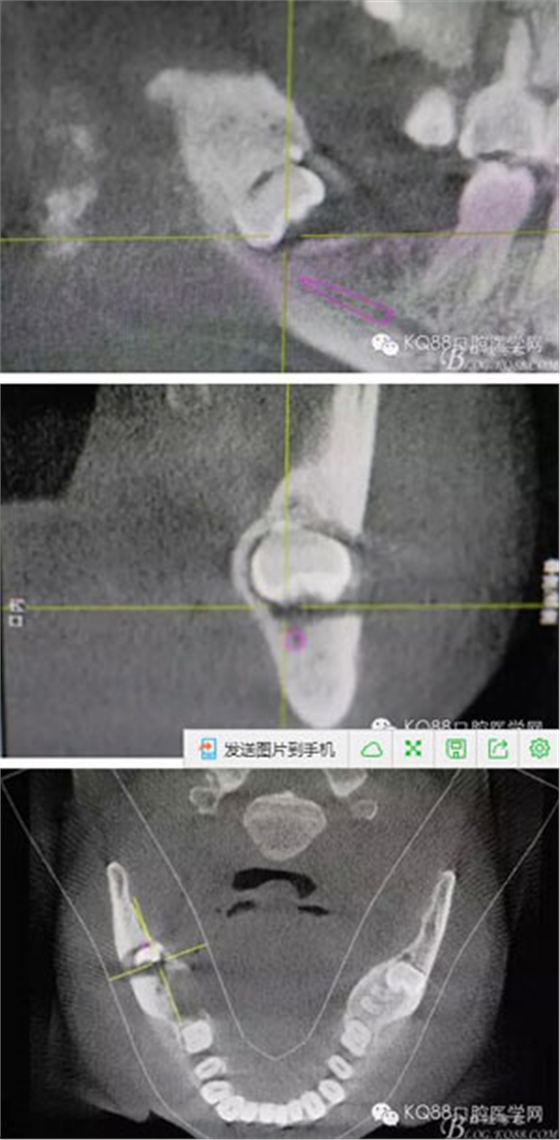

圖3.其他方向的影像檢查:48近中牙冠與下頜管之間無骨壁相隔。